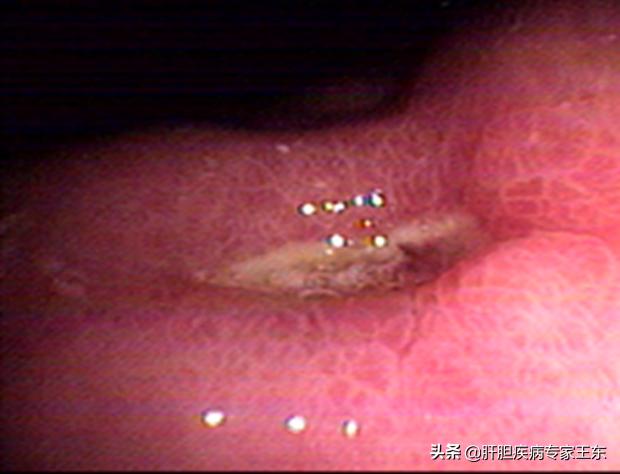

5、食管贲门粘膜撕裂综合征常在剧烈呕吐、腹内压骤增时出现,表现为贲门、食管远端粘膜、粘膜下层纵向撕裂大出血,做急诊胃镜可确诊。

赵先生由于常年的大量饮酒导致了酒精性肝硬化,形成食道静脉曲张,最常出现在食道下方三分之一,由于这些静脉血管暴露在食道内壁,很容易因为压力过大而破裂导致上消化道大出血,表现为吐血、解黑便或血便、心跳加快、脸色苍白、血压降低或休克等症状。